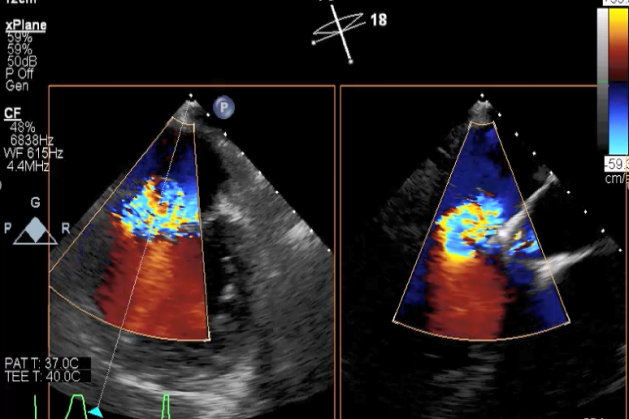

TEE短轴脱垂区域显示(P2、P3区大范围脱垂)

TEE短轴脱垂区域显示(color,血流来源于P2、P3区)

二尖瓣联合部切面引导第一枚XTR夹子转向病变区域并逐渐进入左室

第一枚XTR夹子到达病变区域捕获瓣叶并逐渐夹闭

XTR夹子释放,残余部分返流

三维超声心动图显示第一枚XTR夹子释放,残余返流主要位于外侧

引导第二枚XTR夹子转向外侧残余病变区域并逐渐进入左室

第二枚XTR夹子释放,返流明显减少

三维超声心动图显示第二枚XTR夹子释放